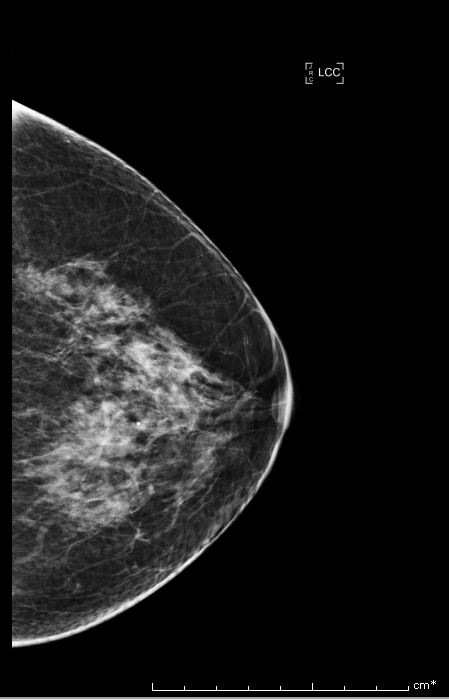

Bi-rads 4 means that the findings on the image are suspicious and that there is an approximately 20 percent to 35 percent chance that a breast cancer is present.

We proceed to calculate the volume of the tumor contained in the breast from the following Bi-rads 4 breast images.

Similarly, we use the same algorithm to evaluate the tumor volume for 4 Bi-rads 4 images and the results are the following:

| Bi-rads 4 Image | Optimal Threshold | Tumor Volume |

|---|---|---|

| Image 1 | 120.574 | 11% of breast volume |

| Image 2 | 59.9143 | 45% of breast volume |

| Image 3 | 239.696 | 0.24% of breast volume |

| Image 4 | 244.590 | 0.0287% of breast volume |